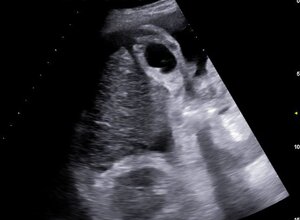

ECOGRAFIA ADDOME